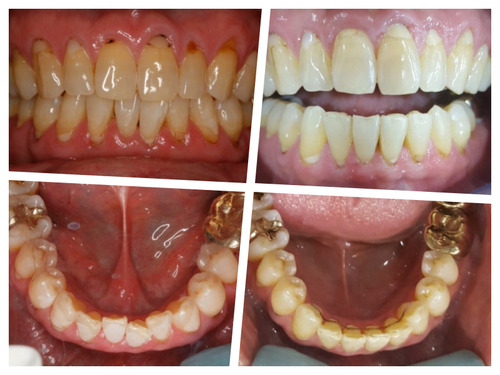

발치 전 사진이 없어서 아쉽지만... 이렇게 한 개 치아를 반드시 발치해야하고 주변치아들이 비뚤다면 정말 교정이 답이 될 수 있다는 생각이 든다. 잇몸이 너무 좋지 않아서 잇몸공간이 눈에 띄기는 하지만 이후 치주 관리도 잘하시고 유지장치로 앞니끼리 고정되어 있으니 예상보다 오래 잘 쓰시고 계신다..